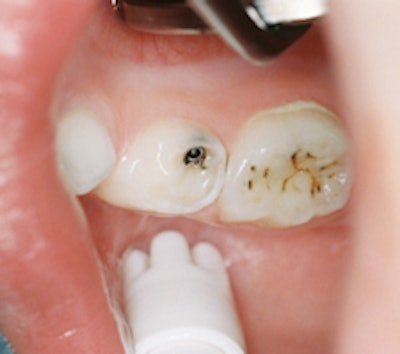

![]()  |

| Two teeth treated with silver diamine fluoride. The tooth on the right shows caries that have been arrested, while the tooth on the left shows arrested incipient caries. Image courtesy of Steven Duffin, D.D.S. |